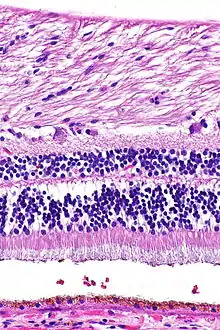

H&E is the combination of two histological stains: hematoxylin and eosin. The hematoxylin stains cell nuclei a purplish blue, and eosin stains the extracellular matrix and cytoplasm pink, with other structures taking on different shades, hues, and combinations of these colors.[5][6] Hence a pathologist can easily differentiate between the nuclear and cytoplasmic parts of a cell, and additionally, the overall patterns of coloration from the stain show the general layout and distribution of cells and provides a general overview of a tissue sample's structure.[7] Thus, pattern recognition, both by expert humans themselves and by software that aids those experts (in digital pathology), provides histologic information.

Hematoxylin principally colors the nuclei of cells blue or dark-purple,[6][15][14] along with a few other tissues, such as keratohyalin granules and calcified material. Eosin stains the cytoplasm and some other structures including extracellular matrix such as collagen[5][7][14] in up to five shades of pink.[8] The eosinophilic (substances that are stained by eosin)[5] structures are generally composed of intracellular or extracellular proteins. The Lewy bodies and Mallory bodies are examples of eosinophilic structures. Most of the cytoplasm is eosinophilic and is rendered pink.[10][15] Red blood cells are stained intensely red.